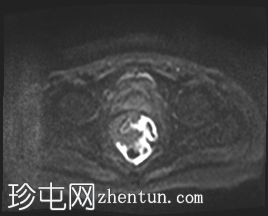

轴位

DWI序列

左侧外侧壁和后壁可见大片缺损,内含气体和粪便,被不规则增厚的肠壁包裹。该缺损在T1加权像上呈低信号,在T2加权像上呈高信号,并伴有明显的扩散受限。